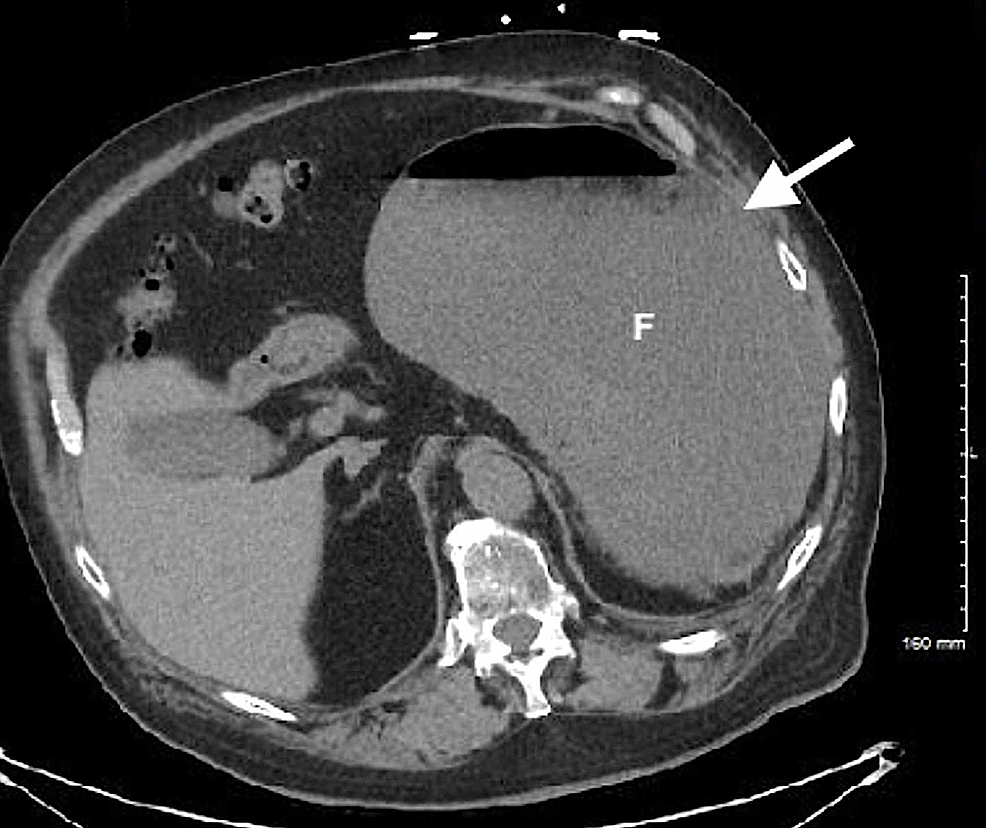

Radiology Gastric Volvulus . — gastric volvulus is characterized by rotation of the stomach along its long or short axis leading to. the radiologists were 90% accurate (55/61 with six misclassifications of gastric volvulus as a hiatal hernia for each reader). — the various imaging appearances of volvulus of the gastrointestinal tract are described, with. — ménétrier disease is a rare overgrowth of gastric mucus cells and can appear with imaging features similar to. — the stomach is suspended at the esophageal hiatus by four ligaments, namely the gastrohepatic, gastrocolic, gastrosplenic and.